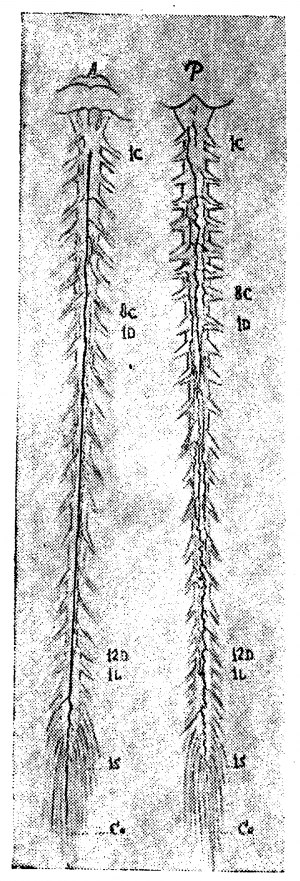

Форма первая. Рис. 6, 7, 8 дают примеры первого типа.

На передней поверхности препарата, изображенного на рис. 6, можно отметить неравномерность калибра среднего ствола, склонность к образованию островков, но, в общем, тракт можно довольно легко проследить на всём его протяжении. На рис. 7 задержка редукции выражена больше: калибр переднего тракта очень мелок, тракт почти прерывается, отклоняясь несколько в сторону; боковые же тракты выражены относительно лучше. Гораздо больше выражена задержка редукции на препарате, изображённом на рис. 8. В нижней части шейного отдела и в грудном отделе средний тракт только отгадывается в системе продольных петель, с частыми боковыми оттоками (ср. верхнюю грудную область, особенно 3-й грудной сегмент, где средний тракт совершенно отходит в сторону, прерывается и оба его отрезка впадают отдельно в параллельные венозные стволики третьего грудного корешка). В области 12-го грудного—1-го поясничного сегмента тракт также отклоняется в сторону, образует островок и почти истощается. В грудной области тракт распадается на два слабых извилистых рукава, образующих длинный островок, а в области 8—11-го сегмента видны даже три параллельных стволика. Оттоки рассеяны, мелки, на одном корешке зачастую видны 2—3 венки. Вена Адамкевича выражена слабо (1 крестцовый корешок слева); боковые тракты едва намечаются прерывистой линией. Эту картину можно считать типичной задержкой редукции, наиболее выраженной для передней венозной сети в ряду изученных нами препаратов.

На рис. 9 видна неравномерность калибра переднего тракта, его извитость, рассеянность оттоков; на рис. 10 видны те же черты: тракт прерывается, извит, образует островки, во многих местах существуют довольно значительные параллельные стволы. Этот рисунок заслуживает внимания: на изображённом здесь препарате задержка редукции выражена и спереди и сзади, а вместе с тем венозные стволы поверхностной сети широки, налиты кровью и при невнимательном взгляде препарат легко отнести к магистральному типу, что было бы, конечно, ошибочно. Развитость стволов, набухлость вен в данном случае являются следствием возрастного изменения и нарушения венозного кровообращения у сердечнобольного (см. ниже гл. IV, болезни сердца).

Задняя поверхность препаратов, изображённых на рис. 6, 7, 8, 10, 11 представляет ещё более резкую картину задержки редукции первичной венозной сети. Так, на рис. 10, несмотря на резкую набухлость вен, в шейной и верхней грудной области почти не выражены продольные стволы: это еще ясней видно на рис. 11, где местами продольные стволы совсем не видны, местами же они только намечаются. Изображённый на рисунке препарат представляет большой интерес с патологической точки зрения и к нему мы вернёмся в гл. IV.

Очень типична картина задержки редукции первичной венозной сети задней поверхности, видная на рис. 7. Мы отмечаем резкую неравномерность калибра и плохое развитие среднего тракта, отклонение от средней линии, перерыв на уровне 7-го — 11-го грудного сегмента, плохую выраженность продольных стволов, местами трудно выделяемых из венозной сети, рассеянность оттоков. Аналогичная картина видна и на рис. 8.

Вторая форма. Магистральный тип поверхностных вен спинного мозга характеризуется двумя основными чертами: хорошей выраженностью среднего тракта и хорошей централизацией оттоков. Боковые продольные тракты обычно только намечаются и, повидимому, вообще редуцируются (рис. 12, 13, 14).

На рис. 12 довольно хорошо выражен магистральный тип вен передней поверхности, строение же вен задней поверхности является переходным. Лучше магистральный тип выражен на обеих поверхностях препарата, изображённого на рис. 13, где почти не видны боковые тракты, а средние тракты представляются хорошо развитыми, относительно равномерными по калибру, оттоки хорошо централизованы. На рис. 14, 15, 16, 17 и 18 можно видеть различные переходные вариации.